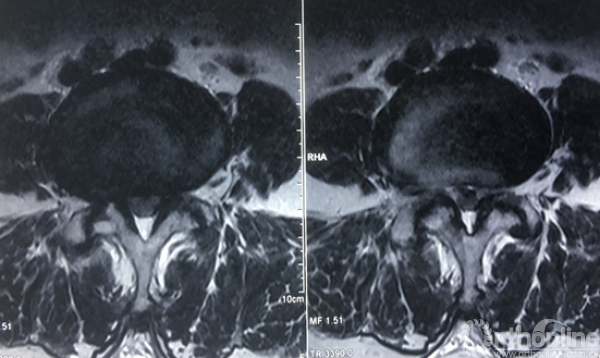

术前腰椎核磁共振横断面